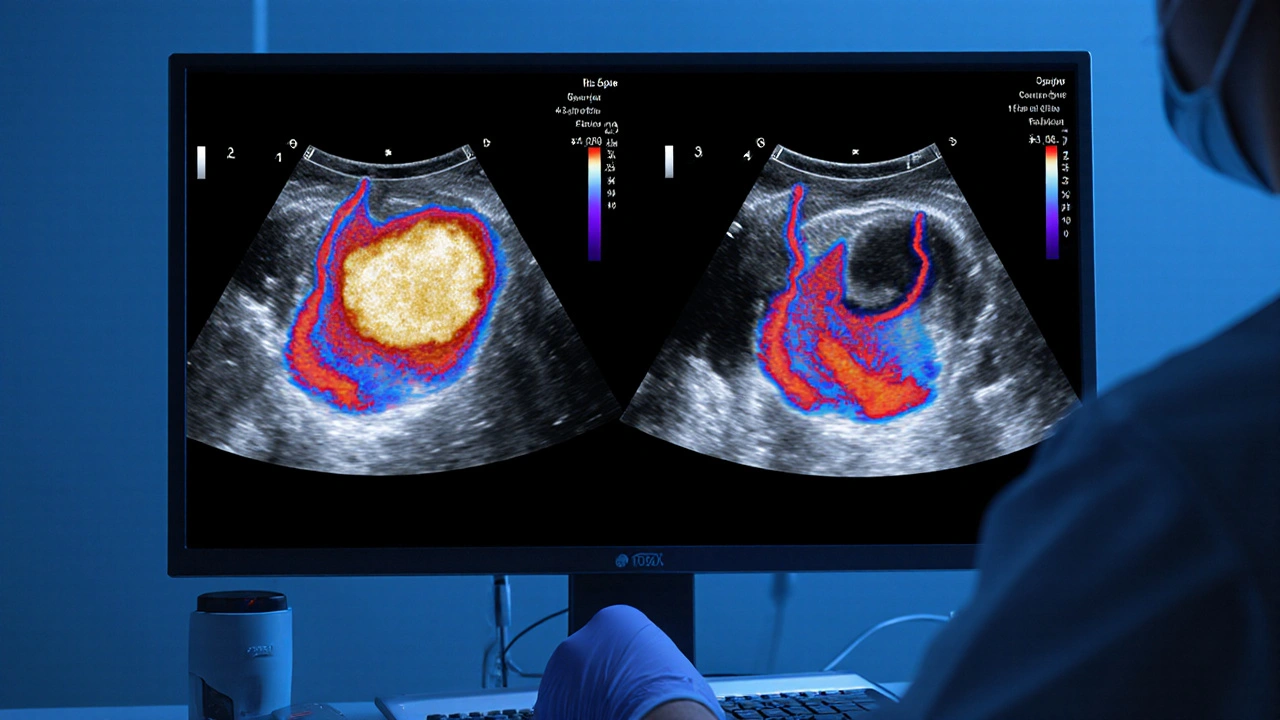

Diagnosing Carotid Artery Disease After a TIA

Timely imaging is the cornerstone of care. The most common modalities include:

Duplex ultrasound | 85‑90% | 95% | Bedside, no radiation, cheap | Operator‑dependent, limited in high bifurcations |

Guidelines recommend that any patient with a TIA get a carotid duplex within 24‑48hours. If the ultrasound suggests ≥50% stenosis, a confirmatory CTA or MRA is usually ordered.